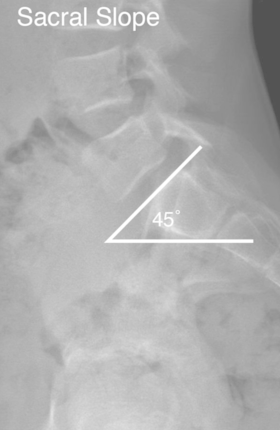

Espondilolisteses

• Qual a definição do Slope Sacral (SS)?

Depende da posição da pelve

• Ângulo entre a linha paralela ao platô superior de S1 e a linha paralela ao solo

• Relação direta com a incidência pélvica e tilt pélvico

• Deve ser 30°

Bizu: Slope Sacral → Solo